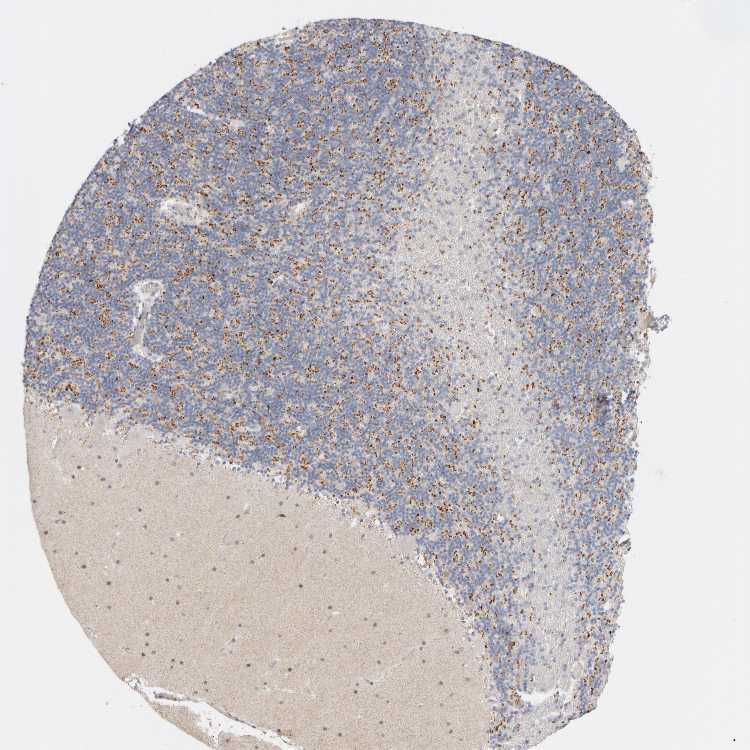

Antibody staining in the annotated cell types in the current human tissue is reported as not detected, low, medium, or high. This score is based on the staining intensity and fraction of stained cells.

On the top, protein expression in current human tissue, based on all annotated cell types, is reported with the units not detected (n), low (l), medium (m) and high (h). Underneath, protein expression in each annotated cell type are reported using the same units.

Protein expression data is based on knowledge-based annotation. For genes where more than one antibody has been used, a collective score is set.